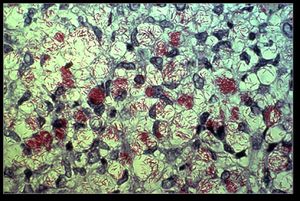

التظاهرات العصبية في هذا الشكل قليلة وهذا الشكل معرض لتظاهرات اشتدادية كظاهرة لوسيو Lucio التي تتصف باندفاعات أغلب ما تكون في الأطراف وبقع حمراء مؤلمة تتطور نحو التقرح والحمامى العقدة الجذامية، ويظهر التشريح المرضي رشاحة أدمية منتشرة من بالعات رغوية كبيرة تحتوي على العصيات الجذامية تسمى خلايا فيركوف.